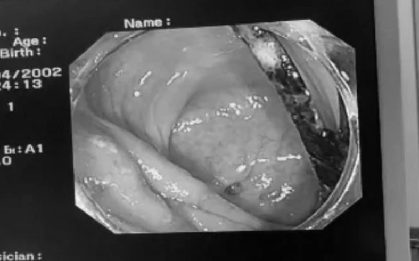

Người đàn ông 33 tuổi bụng phình to như quả bóng, bác sĩ gắp ra thứ "đáng sợ" bên trong

Các bác sĩ đã tiến hành một số xét nghiệm trên nam bệnh nhân 33 tuổi, bao gồm cả nội soi và phát hiện ra thứ "không ai ngờ" trong dạ dày của anh.